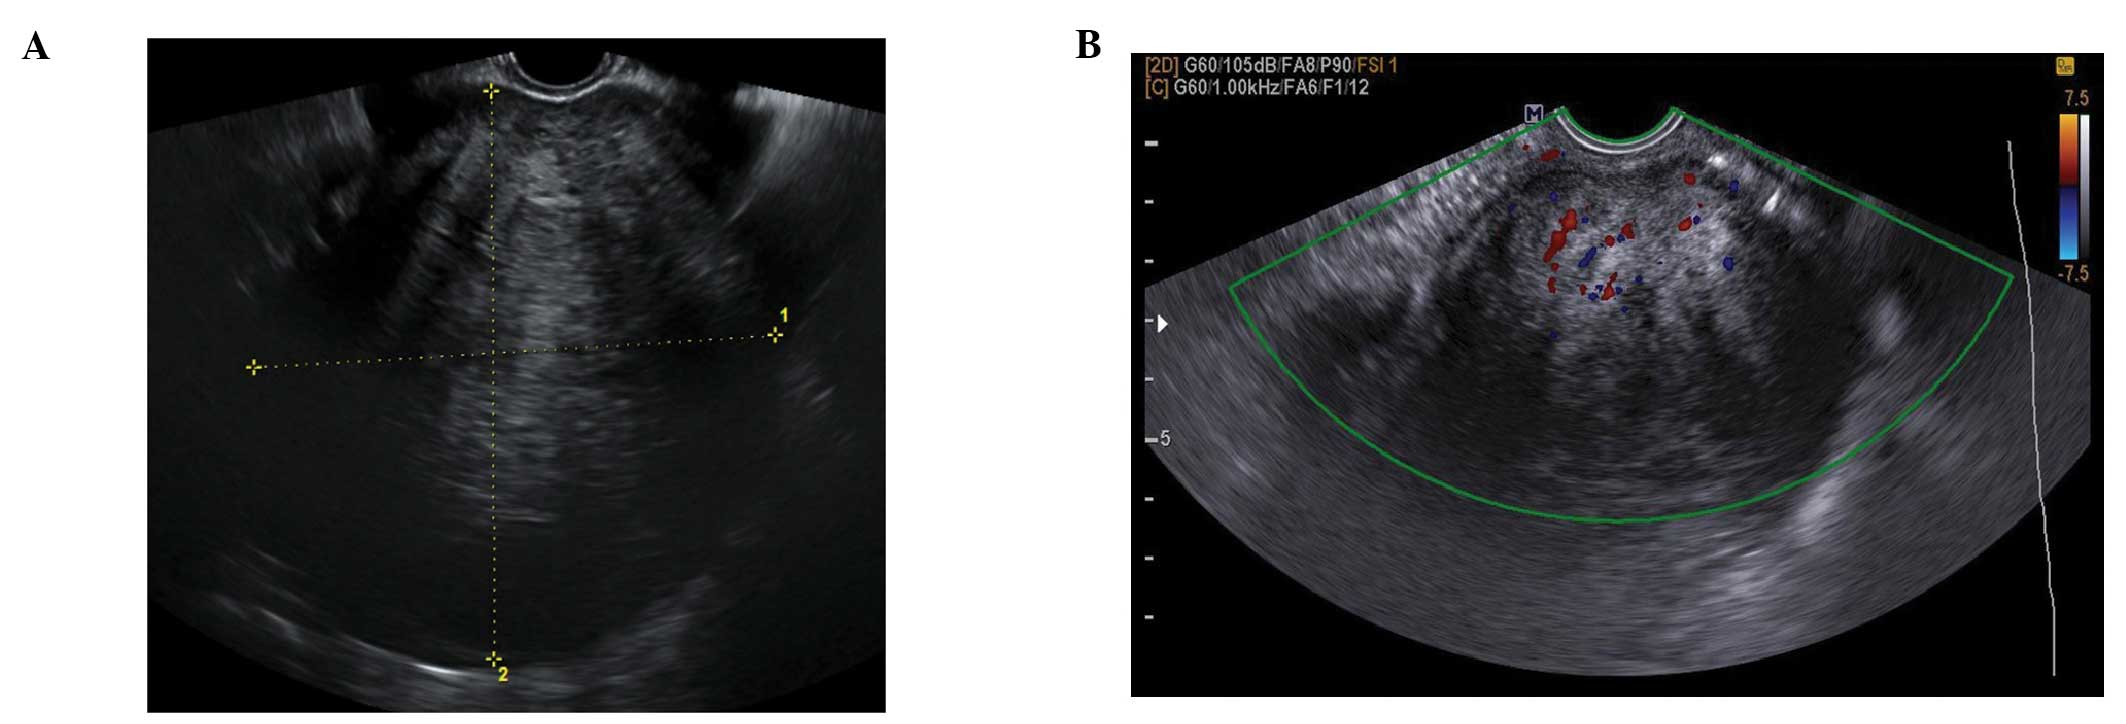

Their characteristic sonographic appearance is of a round or oval solid tumor, with regular margins. They may have stripy acoustic shadows, but these are present in just a small percentage of cases (15,36,37) (Fig. 18). Fibromas and fibrothecomas can also show cystic areas, due to hemorrhage, edema or necrosis within the stromal tissue (Fig. 19). Doppler findings are variable, but frequently the lesions show little peripheral vascularity (36,37) (Fig. 18).

Figure 18

Typical round regular ovarian fibroma with (A) acoustic shadows and (B) minimal peripheral vascularity on color Doppler.